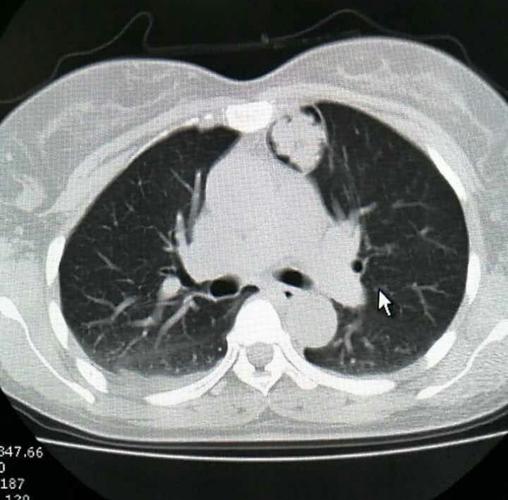

x13664左肺上叶占位病灶